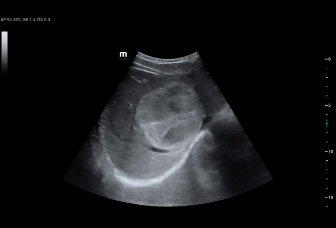

КУУЗИ: метастатический рак печени